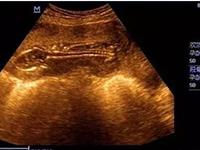

性别选择一直以来都是一个备受关注的话题,尤其是在希望拥有特定性别孩子的夫妇中间。有人坚信,调整身体PH值可以增加生男孩的机会。然而,这一观点存在争议。那么,碱性身体更容易怀男孩吗?科学吗?本文将对这一话题展开探讨,并从科学角度分析碱性身体与胎儿性别之间可能的联系。

碱性身体理论源于一种普遍认为男性精子更喜欢碱性环境的观念。根据这一理论,如果女性能够调整自身的身体PH值,使其更加碱性,那么就能够增加男性精子的生存能力和受孕机会,从而增加生男孩的概率。